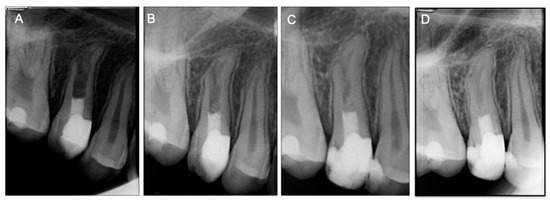

After 2 weeks, the patient developed spontaneous pain, swelling, and a sinus tract. At this time, the surgical endodontic treatment was proposed and explained to the patient and parents. After informed consent was obtained, the surgical procedure was performed by the same Endodontist who performed earlier the apical barrier. Anesthesia was achieved with 2% lidocaine with 1:80,000 epinephrine (XylestesinTM, 3M ESPE, Neuss, Germany), and an Ochsenbein Luebke flap was raised. Following flap retraction, the lesion was accessible and the granulation tissue was carefully removed by curettage. Approximately 2 mm of the root-end was resected with a surgical bur in an air impact high-speed handpiece. After root-end resection (~2 mm), the previous Biodentine barrier was inspected under magnification—nor voids nor chromogenic pigmentation or discoloration detected—as well as mechanically tested with a probe to evaluate its resistance and the lack of voids showing a well condensed barrier and for these reasons no retrograde root-end filling was done. The flap was repositioned and sutured (Figure 3G). One week later, the patient returned with no signs or symptoms, and a resin-based composite (SDRTM flow and Spectrum®) was placed into the root canal structure above the apical barrier all the way to the incisal edge. The resected apical root portion was processed for histologic evaluation. Histopathological assessment of the apical root fragment removed during the surgical root canal treatment was performed (Figure 4). Staining with hematoxylin and eosin (H&E) depicts the presence of a root tip, with pulp tissue at the main foramen as well as small foramina, surrounded by dentin and cement. The presence of a giant multinucleated cell in the pulp tissue near the major foramen shall be emphasized. Granulation tissue was observed in and around the excised root tip.

Furthermore, our findings provide evidence that in clinical case 2, the mineralized structures observed radiographically had histologic features of a root tip—composed by cellular cementum, periodontal ligament, dentin, predentin with an intact odontoblastic layer, and, in some cases, the presence of apical foramen were also seen. Thus, according to our findings, it is reasonable to suggest that even when partially or completely detached from the main root, the apical papilla associated with HERS preserves their potential of continuing root development [18]. These findings confirm the results observed in a study by Yang et al. [27] that the separation of the soft tissues from mineralized tissues and their development as an independent root tip was associated with HERS injure and its following detachment caused by the apexification procedure.

Figure 4. Histologic microphotographs of the apical fragment surgical removed during the apical surgery of the Case 2. Histologic sections depict the presence of mineralized tissue with the ordinary structure of a root apex (due to mineralization of the apical papilla): (A) small magnification of apical root tip with pulp tissue at the main foramen as well as small foramina (f), surrounded by dentin (d) and cement (c). Fragments of granulation tissue (gt) can be observed on the outside root wall. (B) High magnification of the cementum–dentin junction (CDJ) of the main canal showing the connective pulp tissue (p), cementum (c) on the inner portion and dentin (d). (C) High magnification of foramina depicting in the central portion the pulp tissue surrounded by dentin (d) on the right upper side and by cement (c) on the lower left side. The dentinal tubules are show in a transversal section. (D) High magnification of the apposition/formative phase during cementum formation. Hematoxylin mineralization granules (blue arrow) can be observed on the non-mineralized cementum matrix (cm) and cementoblasts (cb). (Hematoxylin–eosin, H&E).